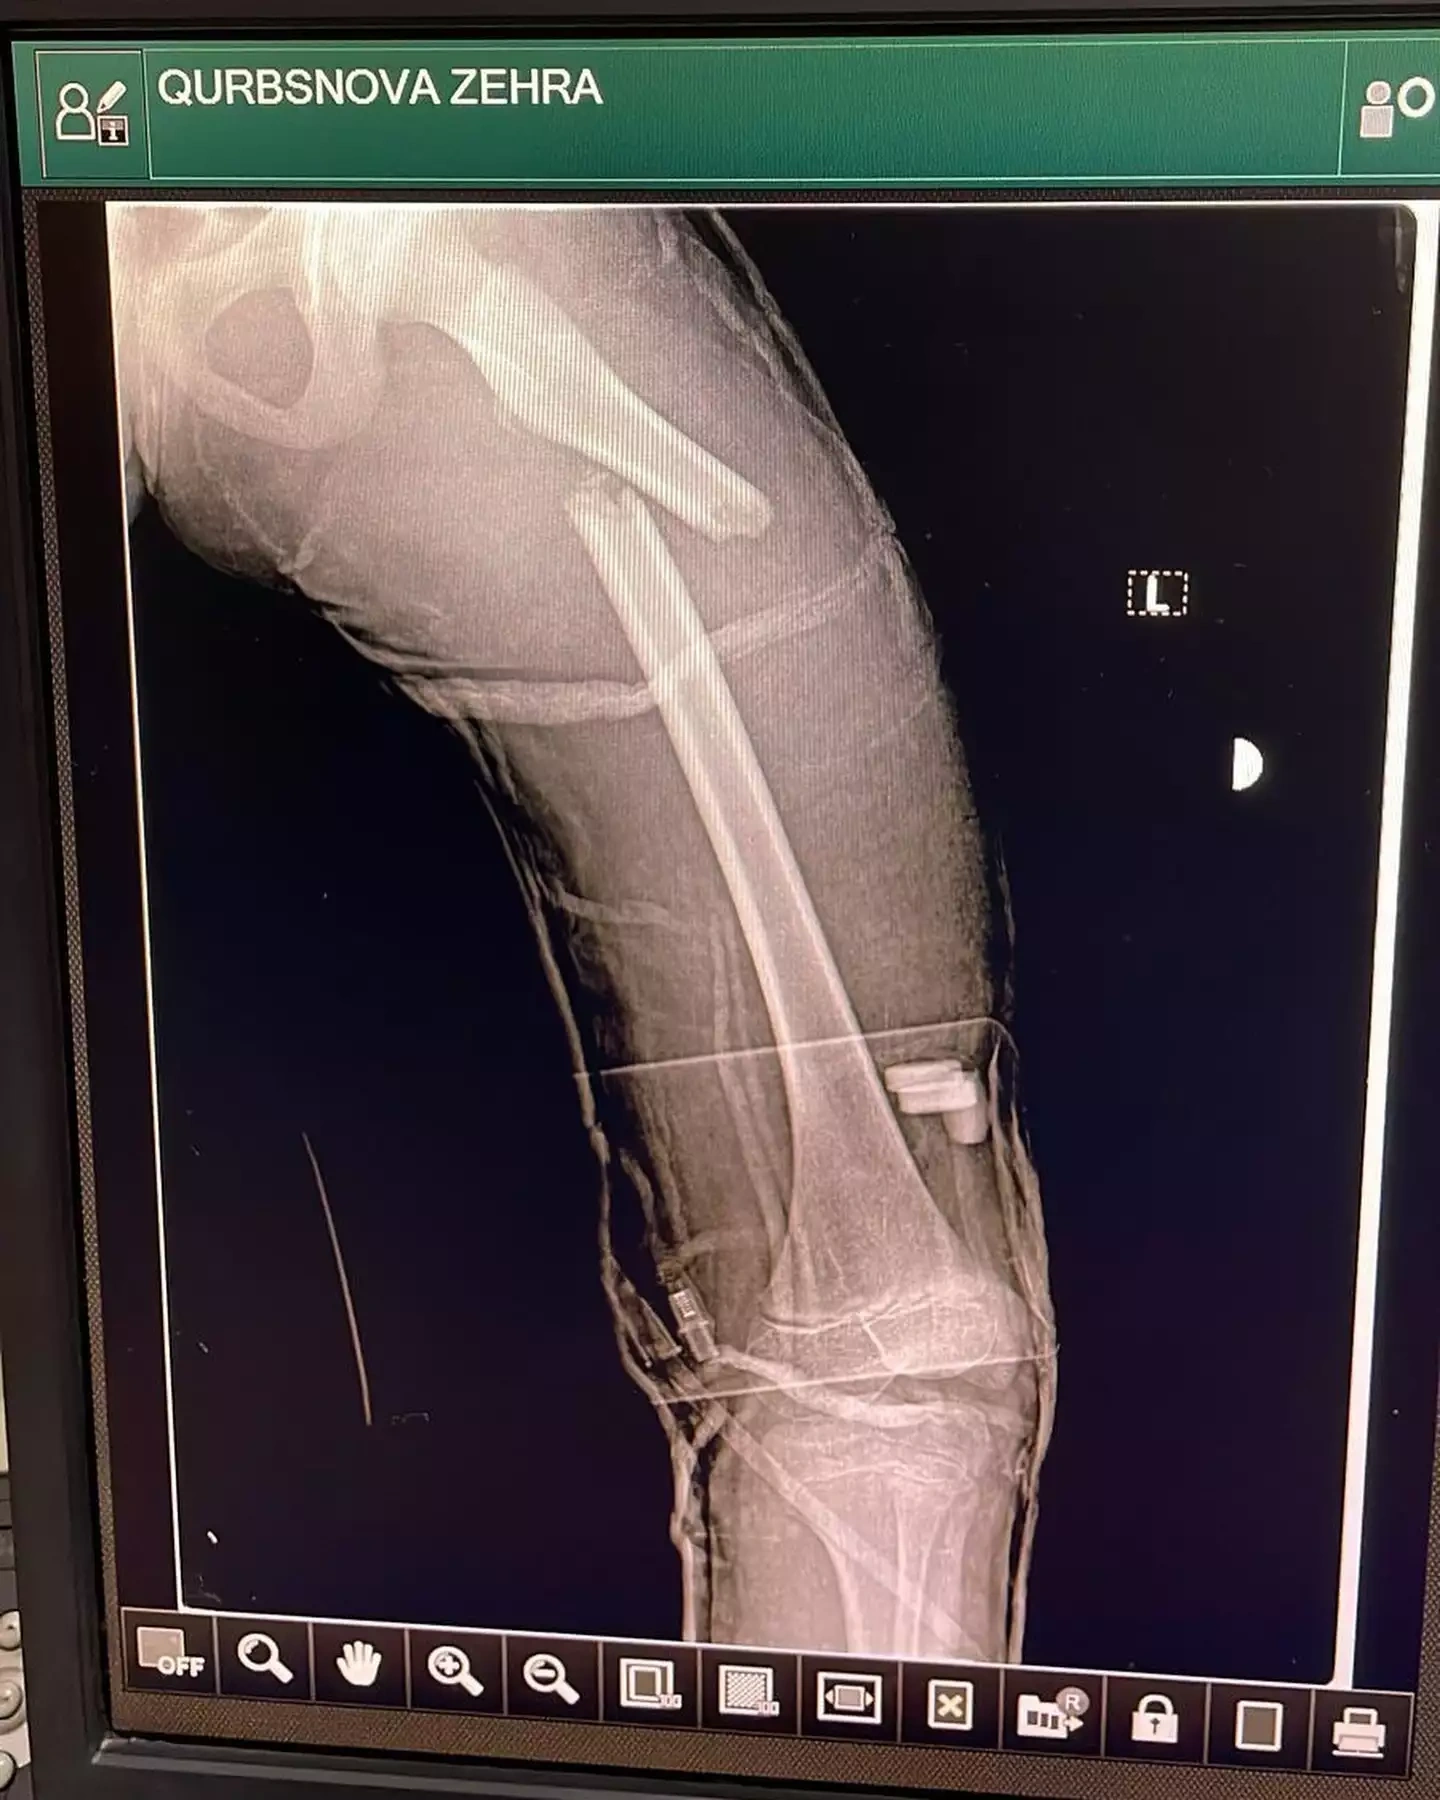

Hadisədən yalnız iki azyaşlı xilas ola bilib. Nərmin bildirib ki, onların da səhhətlərində ciddi problemlər yaranıb və maddi dəstəyə ehtiyacları var.